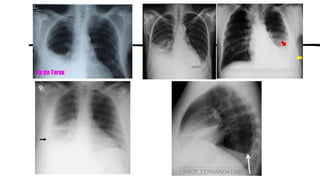

AP – DECÚBITO LATERAL

(Método de Laurell)

FATORES TÉCNICOS:

• DFR mínima − 183 cm

• Tamanho do RI – 35 × 43 cm (14 ×

posicionando

transversalmente (em relação à

posição do paciente)

• Grade

• Sistemas analógicos ou digitais –

faixa de 110 a 125 kV

• Identificar como “decúbito”

Indicações Clínicas

• Pequenos derrames pleurais são

demonstrados pela presença de níveis

hidroaéreos no espaço pleural.

•Pequenas quantidades de ar na

cavidade pleural podem indicar um possível

pneumotórax.

PROF. FERNANDA LIMA

POSIÇÃO

OBLÍQUA

Posições oblíquas do tórax, abdome ou pelve são definidas pela

parte mais próxima ao RI ou pela parte do corpo pela qual o RC sai.

Posições oblíquas posteriores direita e esquerda (OPD e OPE)

• Descreve as posições oblíquas específicas no qual o lado

posterior esquerdo ou direito do corpo está próximo ao RI.

Obs: Também podem ser referidas como incidências

oblíquas AP, pois o RC entra numa superfície anterior e sai

posteriormente.

Posições oblíqua anterior direita e esquerda (OAD e OAE)

• Esses termos se referem às posições oblíquas nas quais o

lado anterior direito ou esquerdo do corpo está próximo ao

RI, e pode estar em posição ereta ou recumbente. Obs:

Também podem ser descritas como incidências oblíquas PA,

se a posição de esclarecimento for incluída, tais como as

posições OAD ou OAE.